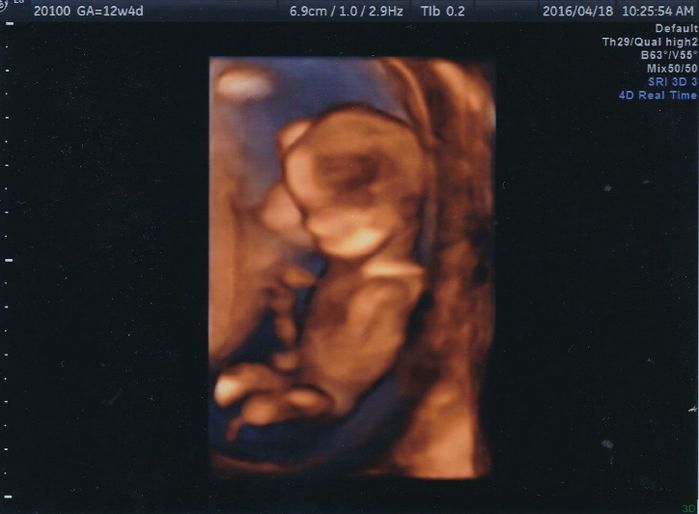

妊娠12週目のエコー写真

こちらの写真では、赤ちゃんの心拍が写っています。頭が左で体が右です。食事内容や生活習慣に加えて、仕事量が多くなりすぎないように気をつけていました。

こちらの写真では、頭と体、手足が分かります。両足の付け根の辺りから上に向かって伸びているのがへその緒で、自分とのつながりが写真で見えて何だか不思議な気持ちになりました。

こちらは4Dの拡大版です。先ほどの写真よりも、へその緒のねじれている感じが少しですが読み取れます。